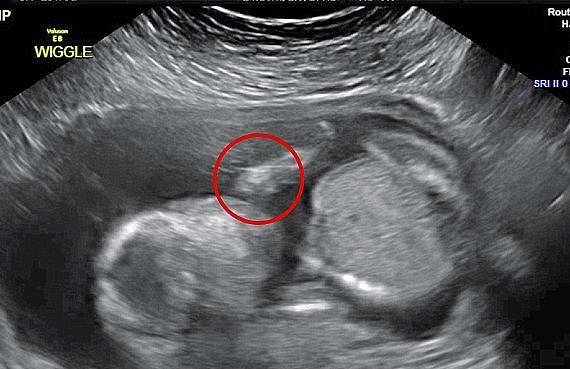

▼超音波照片经常会出现有趣的画面,之前就有人发现一个恶魔正在看自己刚刚一个月大的宝宝。